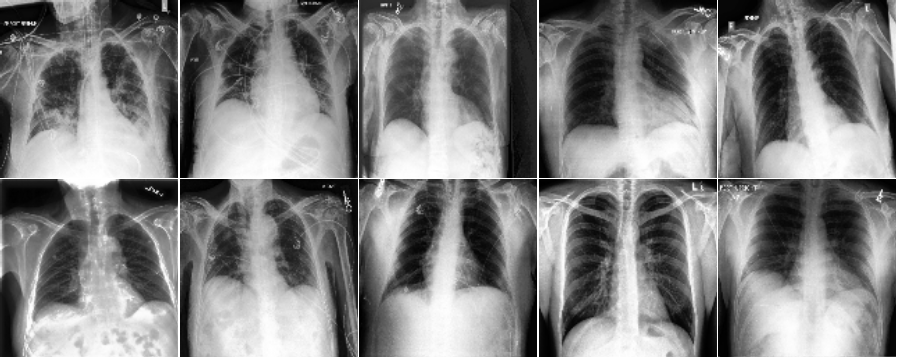

This section presents visualization of the proposed architecture. These visualizations are presented in Figure 5. Unlike Figure 2 that is an executive summary with each position representing many samples, these visualizations in Figure 5 are sample-wise plots. In other words, the 10 original images that are sized 128 by 128 in Panel A and Panel B are the same samples in the second row, 1st Conv. Layer, and the third row, 2nd Conv. Layer.

Visualization Interpretation The plot in Figure 5 of the original images for COVID-19 patients has grey and cloudy textures in chest area. Because an X-ray picture is at its brightest when most of the light beams emitted are bounced back from the object, we can observe bones to be the color “white” while the margin to be completely “black”. For muscle and organs inside human body, X-ray beams that are emitted can only partially be collected and this causes the greyscale on the X-ray images in chest area. For COVID-19 patients, there are grey and shaded area in the chest X-ray pictures. This is due to the inflammatory fluid when patients exhibit pneumonia-like symptoms. The fluid inside chest area is a consequence of human immune system fighting against outside diseases. This shaded (as seen in Panel A of Figure 5) prevents us from observing the clear location of lungs. This is different in Panel B where the lung areas are dark and almost black, because a healthy lung is filled with air (i.e. normal cases and X-ray image presents color black). The black and white contrast in the two panels is directly related to how much inflammatory fluid there is in human lungs. This contrast translates to greyscale on pictures and it is directly related with COVID cases and non-COVID cases (i.e. response variable ). The same contrast can be seen using the new variables (these are ’s based on equation 4) in the 1st Conv. Layer (sized 61 by 61). For COVID-19 patients, the lung area is cloudy and unclear while the healthy cases it is clearly visible. This is not a surprising coincidence because the proposed new variable modules, ’s, are engineered using equation 4 which relies on the response variable in training set. The images sized 61 by 61 from the proposed algorithm is a direct translation of not only the original pixels but also response variable. In other words, this visualization presents how I-score sees image data.

| Row (b) |  |

|

| 2nd Conv. Layer: 30 by 30 | 2nd Conv. Layer: 30 by 30 | |

| (Starting Point = 6, Window 2 by 2, Stride = 2) | (Starting Point = 6, Window 2 by 2, Stride = 2) | |

| Remark: variables | variables | |

| Same 10 images above with 900 variables | Same 10 images above with 900 variables | |

| Labels predicted using Model 4 | Labels predicted using Model 4 | |

| Row (c) |  |

|

Discussion for Figure 5.

This figure presents visualization summary for 10 randomly sampled images from COVID class and non-COVID class (each has 10). Panel A is for COVID patients and Panel B is non-COVID people. The first row plots the original images that are sized 128 by 128. The 1st Conv. Layer generates new variables. We plot the same 10 images from both classes using these 3,721 variables in the second row. We also print the predicted COVID probabilities on top left corner of each image. The 2nd Conv. Layer generate variables. We plot the same 10 image samples from both classes using these 900 variables in the third row. We also print the predicted COVID probabilities on top left corner of each image assuming using only these 900 variables as predictors. The plot of the original images for COVID-19 patients has grey and cloudy textures in chest area. This is due to inflammatory fluid when patients exhibit pneumonia-like symptoms. This shaded (as seen in Panel A) prevents us from observing the clear location of lungs. This is different in Panel B where the lung areas are dark and almost black which means the lung is filled with air (i.e. normal cases). The black white contrast in the two panels is directly related to how much inflammatory fluid there is in human lungs which translate to greyscale on pictures. The same contrast can be seen using the new variables (these are ’s based on equation 4) in the 1st Conv. Layer (sized 61 by 61). For COVID-19 patients, the lung area is cloudy and unclear while the healthy cases it is clearly visible.

|

Discussion for Figure 5.

Original Images to 1st Conv. Layer. The input images are sized 128 by 128. With the 1st Conv. Layer constructed, we have new variables. We trace back to the same samples as shown in the first row of Figure 5 and use these 3,721 variables only. When we plot these samples with these new variables, we resize them back in matrix form of 61 by 61. Panel A is for COVID class and Panel B is for non-COVID class. In addition, we use Model 1 in Table 4 to produce the texts that states predicted probability of COVID class. The red color implies ground truth to be COVID class (Panel A) and the green color implies ground truth to be non-COVID class (Panel B).

1st Conv. Layer. to 2nd Conv. Layer. From the resulting matrix of the 1st Conv. Layer, we are left with 3,721 variables. We go through the proposed design in Table 4 and we create a new convolutional layer, i.e. 2nd Conv. Layer. This new layer has variables. We take the same 10 sampled images from before and we use these 900 variables to present these images. In this presentation, we resize these 900 variables into shape 30 by 30. In other words, we get a smaller matrix that we can plot that exhibit mini version of similar patterns as before. We use Model 4 to generated the predicted probabilities. These probabilities are printed on the top left corner of each image and they are color coded similarly as before (red probabilities have ground truth of COVID class while green probabilities have ground truth of non-COVID class).